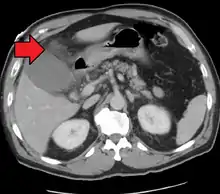

| Acute cholecystitis as seen on CT. Note the fat stranding around the enlarged gallbladder. | |

Right upper quadrant abdominal ultrasound is most commonly used to diagnose cholecystitis.[1][26][27] Ultrasound findings suggestive of acute cholecystitis include gallstones, pericholecystic fluid (fluid surrounding the gallbladder), gallbladder wall thickening (wall thickness over 3 mm),[28] dilation of the bile duct, and sonographic Murphy's sign.[13] Given its higher sensitivity, hepatic iminodiacetic acid (HIDA) scan can be used if ultrasound is not diagnostic.[13][14] CT scan may also be used if complications such as perforation or gangrene are suspected.[14]

Acute cholecystitis with gallbladder wall thickening, a large gallstone, and a large gallbladder- Significant gallbladder wall thickening[29]